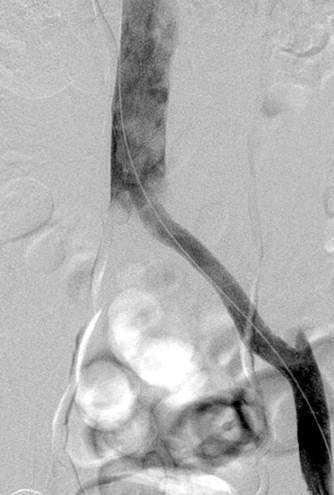

Venografía axial por CT donde se muestra un trombo agudo que va del filtro de VCI  hasta la vena ilíaca interna y externa derecha y la vena ilíaca común izquierda.

Venografía coronaria por CT donde se muestra un trombo agudo que va del filtro de VCI hasta la vena ilíaca interna y externa derecha y la vena ilíaca común izquierda.